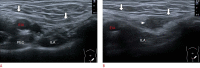

Inguinal hernia is the most prevalent type of abdominal wall hernia. Indirect inguinal hernia is twice as common as direct inguinal hernia. Computed tomography and magnetic resonance imaging can be used to evaluate inguinal hernia, but these modalities are greatly limited by their cost and availability. Ultrasonography has emerged as the most convenient imaging tool for diagnosing inguinal hernia due to its advantages, such as portability and absence of radiation. The present pictorial review presents an overview on the use of ultrasonography in the evaluation of inguinal hernia with a particular emphasis on the regional anatomy, relevant scanning tips, identification of subtypes, postoperative follow-up, and diagnosis of pathologies mimicking inguinal hernia.